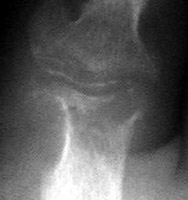

Charcot: AP - Dislocation tarsometatarsal joint

+++